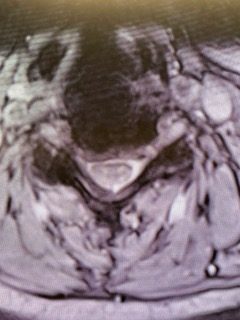

(Fig. 2) Axial T2 cervical MRI at C4-5 demonstrating significant osteophytic disease with bilateral neural foraminal compression of the C5 nerve roots, right greater than left.